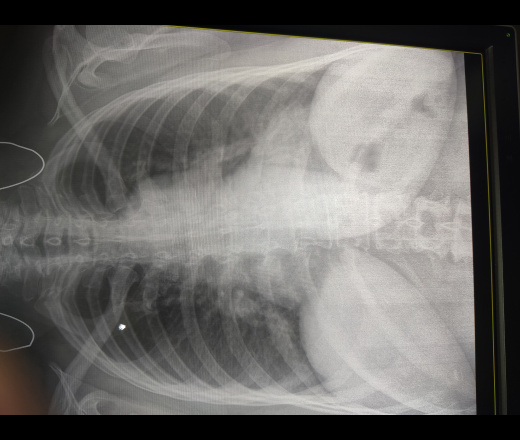

Пол пациента: Женский пол Тип патологии: Инфекция Область исследования: Грудная клетка и верхние дыхательные пути Методы исследования: Rg Здравствуйте, женщина 59, делали снимок перед госпитализацией, анамнеза нет, ушла до того как успел опросить. Не нравяться нижние отделы. Пневмония? Флюрография год назад https://radiomed.ru/sites/default/files/styles/case_slider_image/public/user/56988/snapmarkup_20233327_083350.png?itok=pI096H5u ID:92078 Цель публикации: Консультация Tue, 28/03/2023 - 09:54 #1 Сергей Кузьминов Offline Last seen: 1 year 3 weeks ago Joined: 06.10.2012 - 15:51 Posts: 11813 Нету пневмонии.

Нету пневмонии.